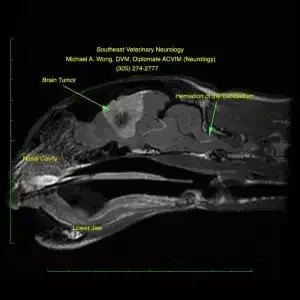

Mri Dog Brain Glioma

MRI of the brain of a dog showing a glioma.